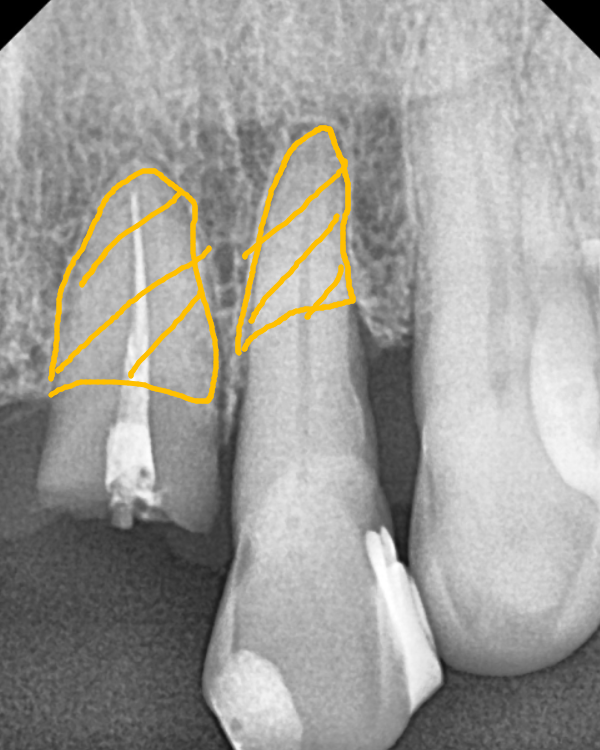

CT 상으로 확인한 오른쪽 위 송곳니(#13)는

뿌리 끝 염증으로 잇몸뼈까지 녹아있었죠.